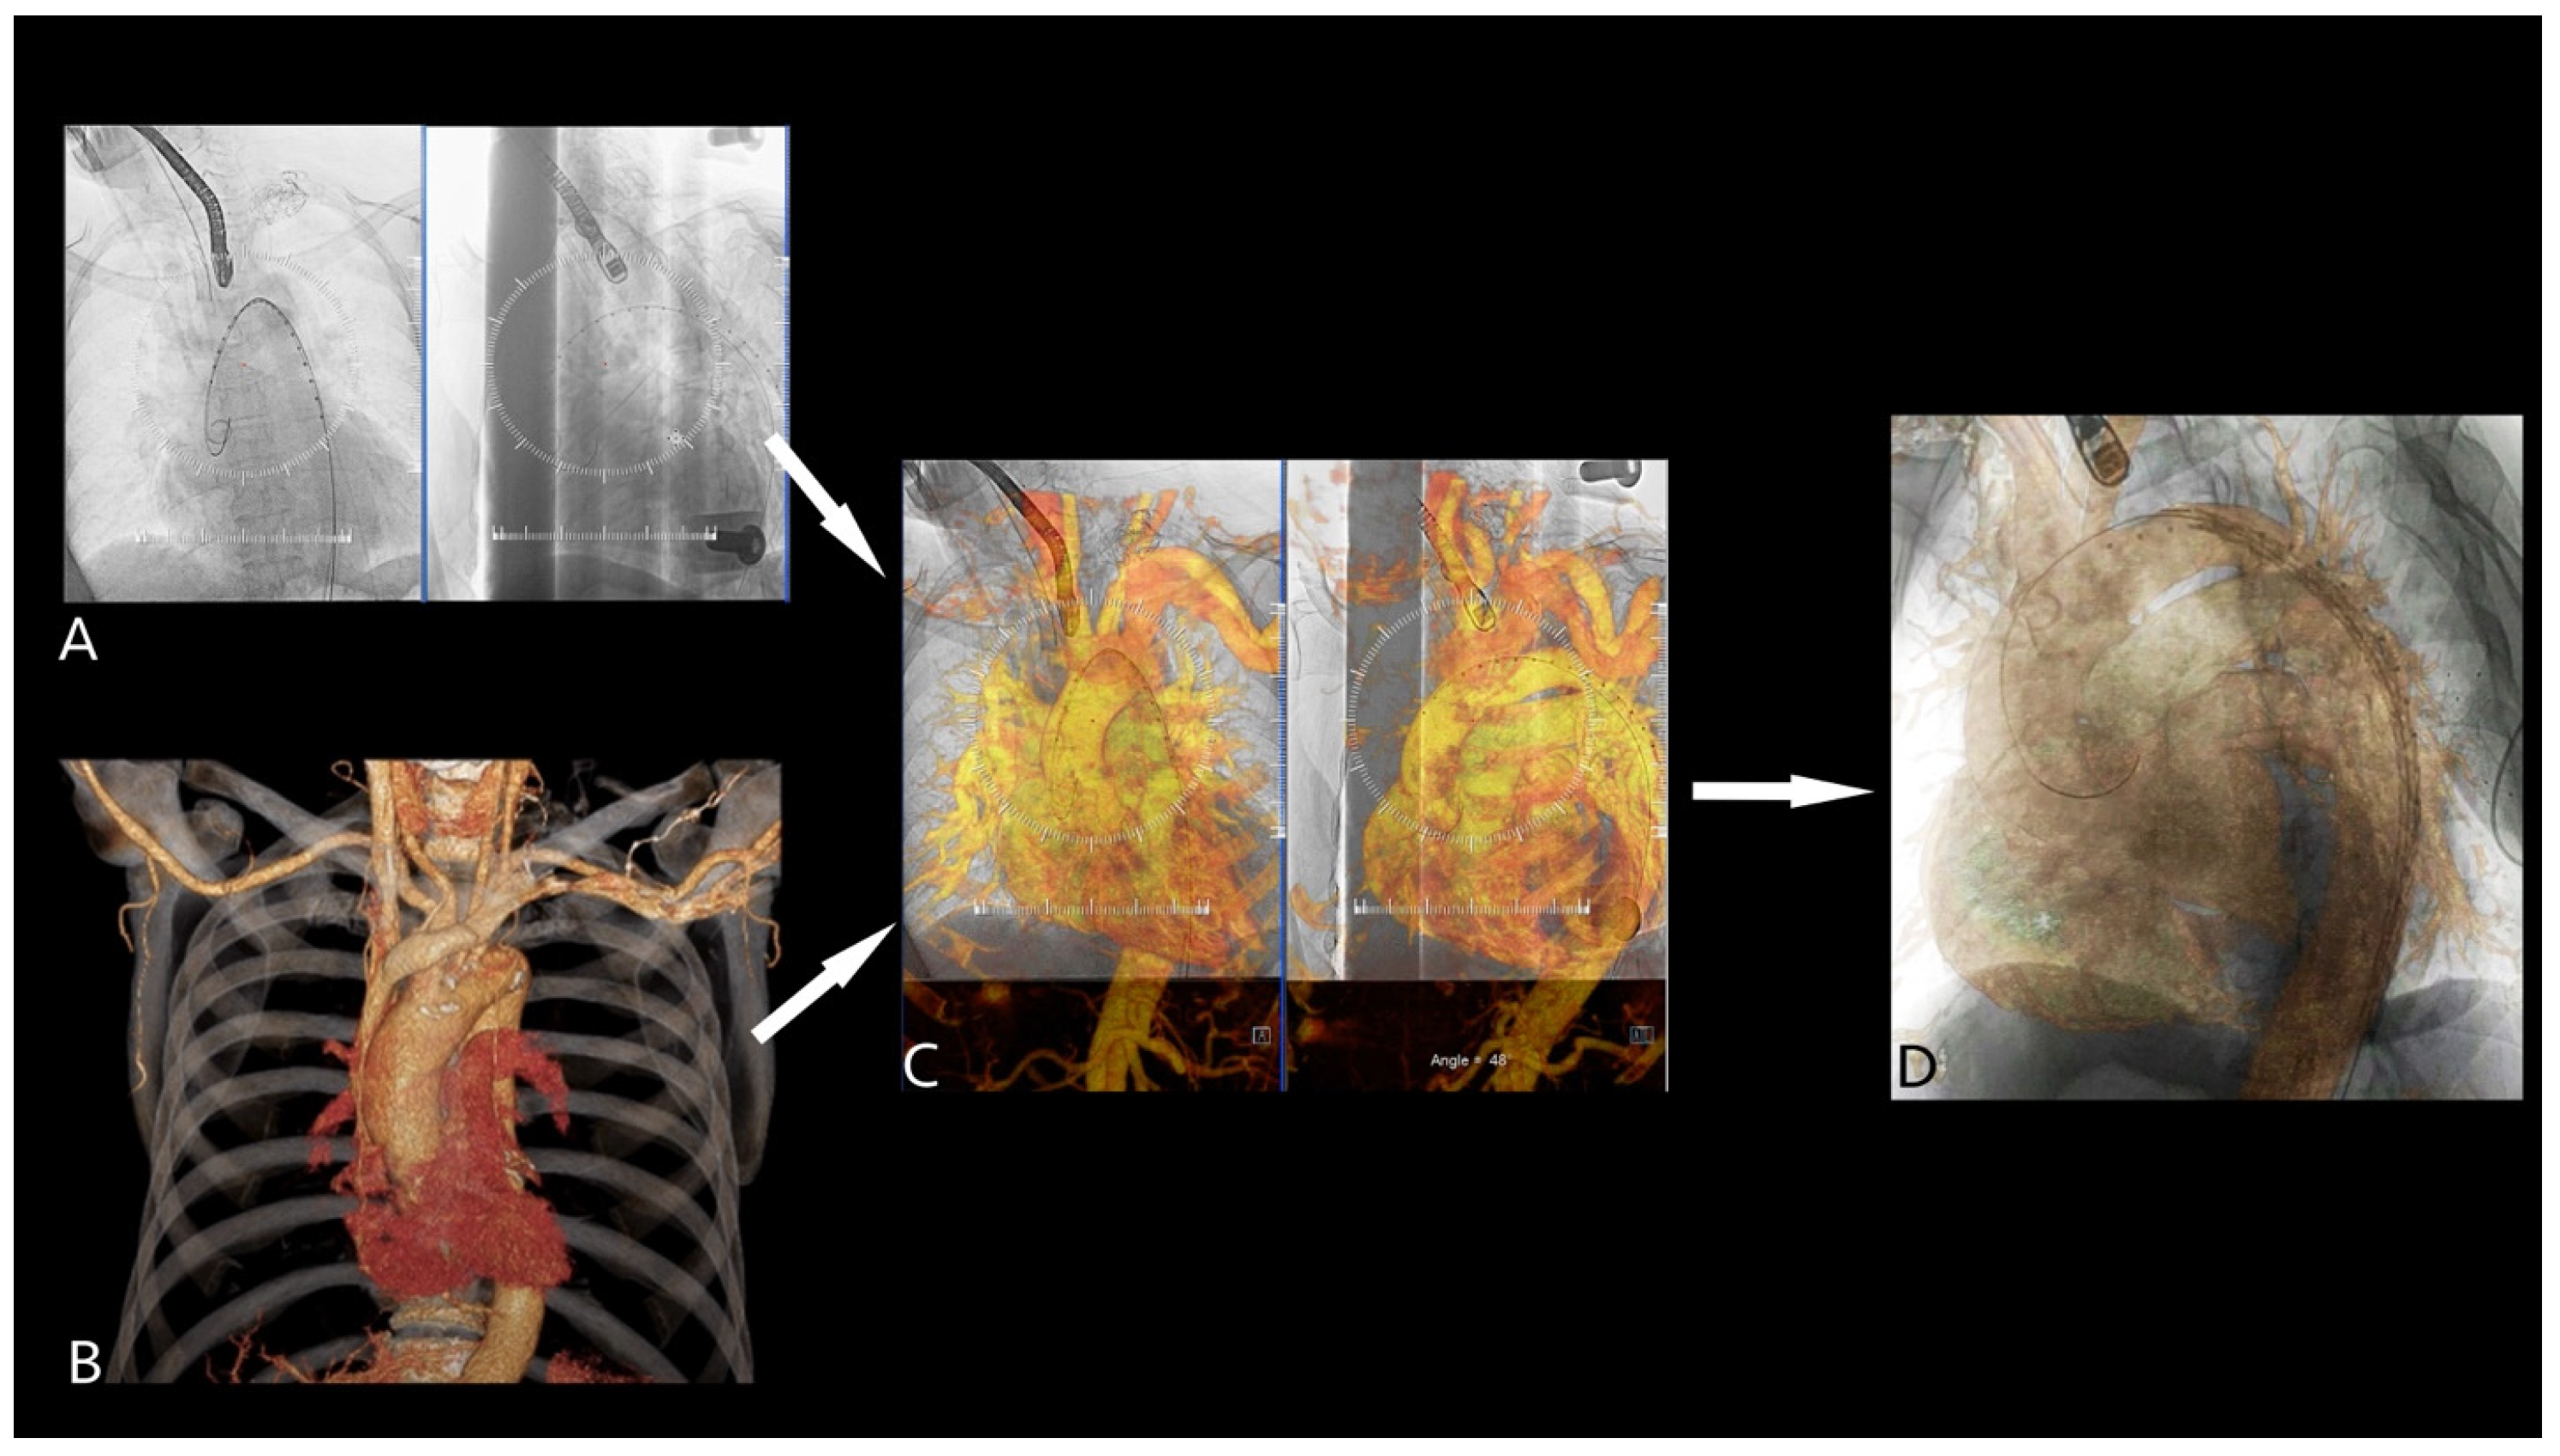

2.4. 2D3D Fusion Technique

2.5. 3D3D Fusion Technique